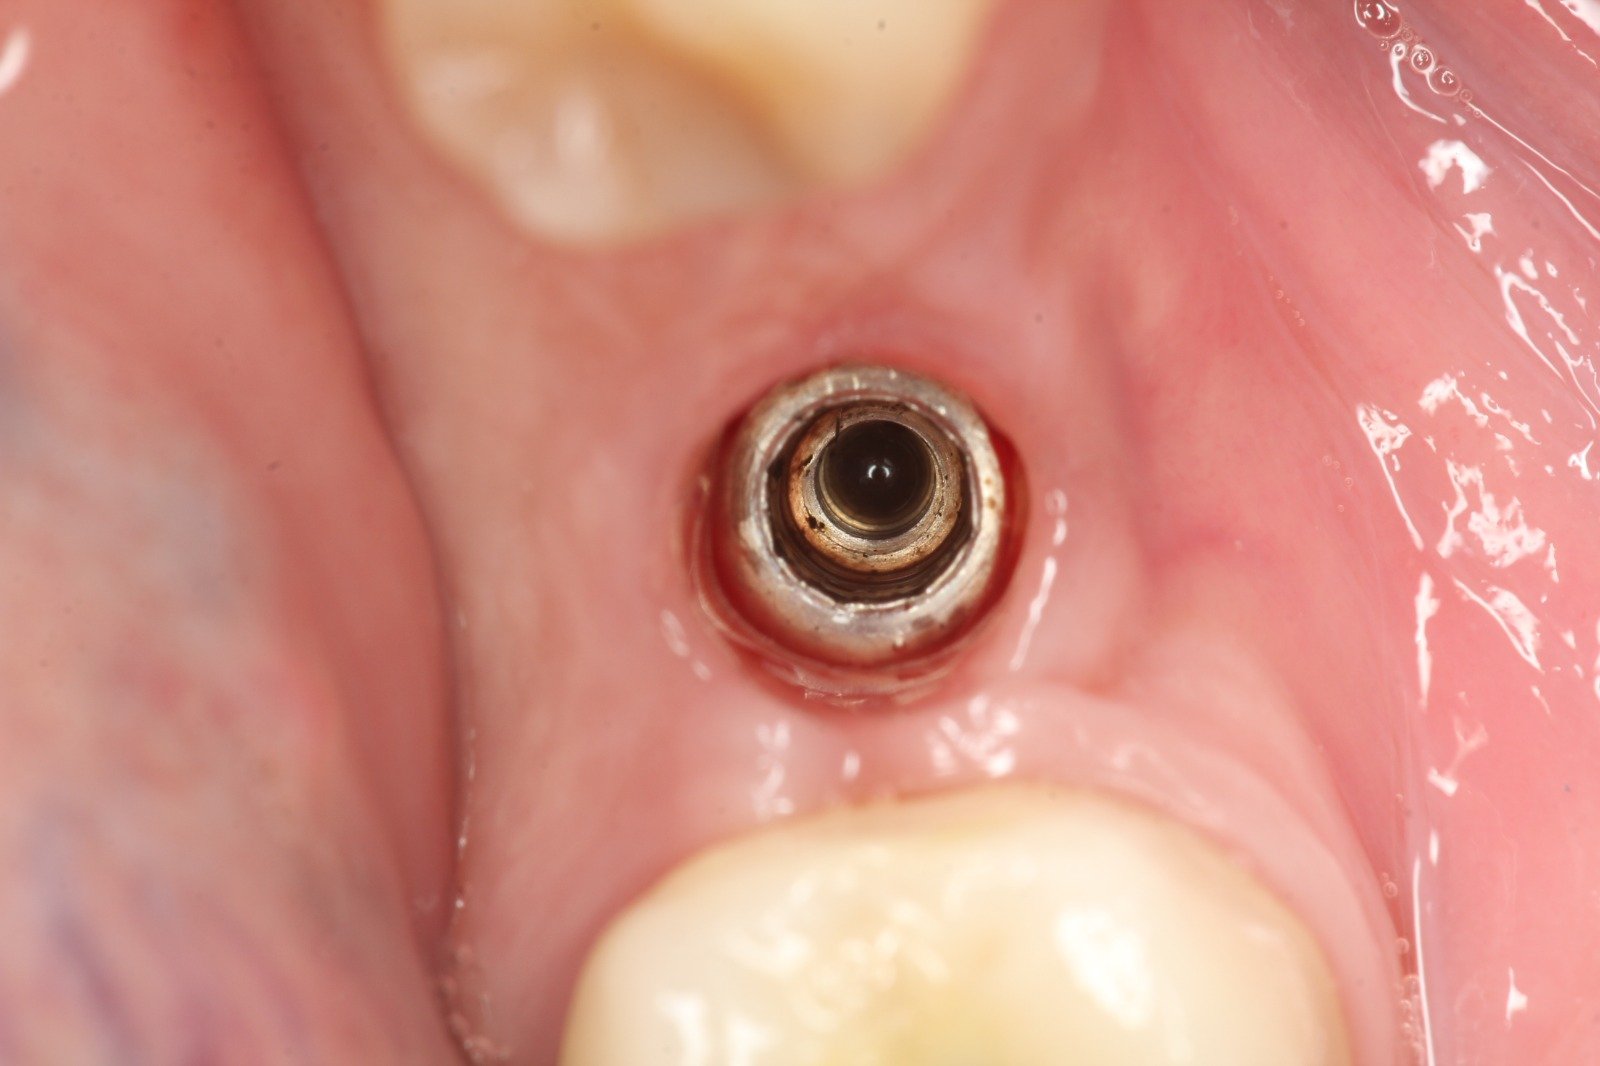

Varón de 38 años. Asegura llevar el implante del 21 desde hace aproximadamente 20 años. Lleva una corona cementada con movilidad (por aflojamiento del tornillo del pilar) desde hace unos [...]